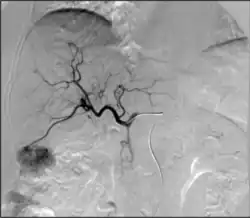

Технология диализатора изначально опережала возможности врачей применять ее к пациентам. В 1920-х годах был создан первый диализный катетер с использованием тонких хрупких стеклянных трубок. Ранние методы требовали хирургического разреза для доступа к крупным сосудам, что было сопряжено с большим риском сильного кровотечения. Первый относительно постоянный и надежный доступ для диализа — тефлоновый шунт Скрибнера — был изобретен почти 40 лет спустя и позволил пациенту с почечной недостаточностью прожить еще 11 лет. По мере того, как медицина и хирургия становятся все более совершенными, в настоящее время больше пациентов живут с хроническим заболеванием почек, чем когда-либо прежде. Наиболее распространенным видом диализа в Соединенных Штатах является гемодиализ, который может проводиться через несколько типов сосудистого доступа. Предпочтительным методом является артериовенозная фистула (АВФ). Артериовенозные фистулы создаются хирургическим путем путем прямого соединения артерии и вены, чаще всего на руке. Артериовенозный трансплантат (АВТ) работает по тому же принципу, но заполняет зазор между артерией и веной с помощью медицинского протезного шунта. Со временем изменение механики потока может привести к изменениям в пораженных сосудах. Сужение сосудов, тромбоз, аневризмы и псевдоаневризмы являются частыми осложнениями, встречающимися в течение срока службы артериовенозной фистулы или артериовенозной троакарной тугоухости. Интервенционные радиологи могут использовать ангиографию для оценки этих структур (обычно называемую истулограммой) и лечить дисфункциональный доступ с помощью ангиопластики, стентирования и тромбэктомии. Большинству пациентов требуются регулярные обследования и лечение для поддержания работоспособности доступа. По возможности предпочтение отдается артериовенозным фистулярным трубкам, а не артериовенозным ангиопластикам, поскольку они вызывают относительно меньше осложнений и обеспечивают большую проходимость. Инициатива Fistula First направлена на повышение осведомленности врачей и пациентов о преимуществах первой попытки гемодиализа через фистулу.[42] Существует несколько устройств (эндо АВФ), которые используются интервенционными радиологами для чрескожного создания свищей минимально инвазивным способом.